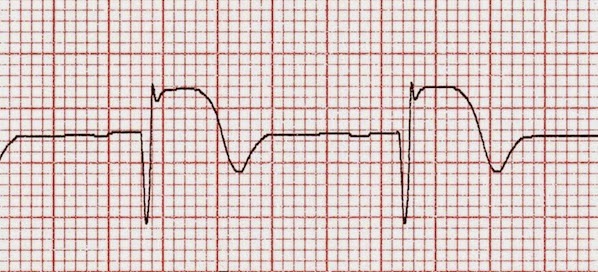

Beta bloqueadores y función cardíaca luego del infarto de miocardio

Un estudio británico de cohortes encontró que el uso de beta-bloqueadores luego de un infarto agudo de miocardio no fue beneficioso en ausencia de insuficiencia cardíaca o de disfunción sistólica del ventrículo izquierdo. JACC, 29 de mayo de 2017